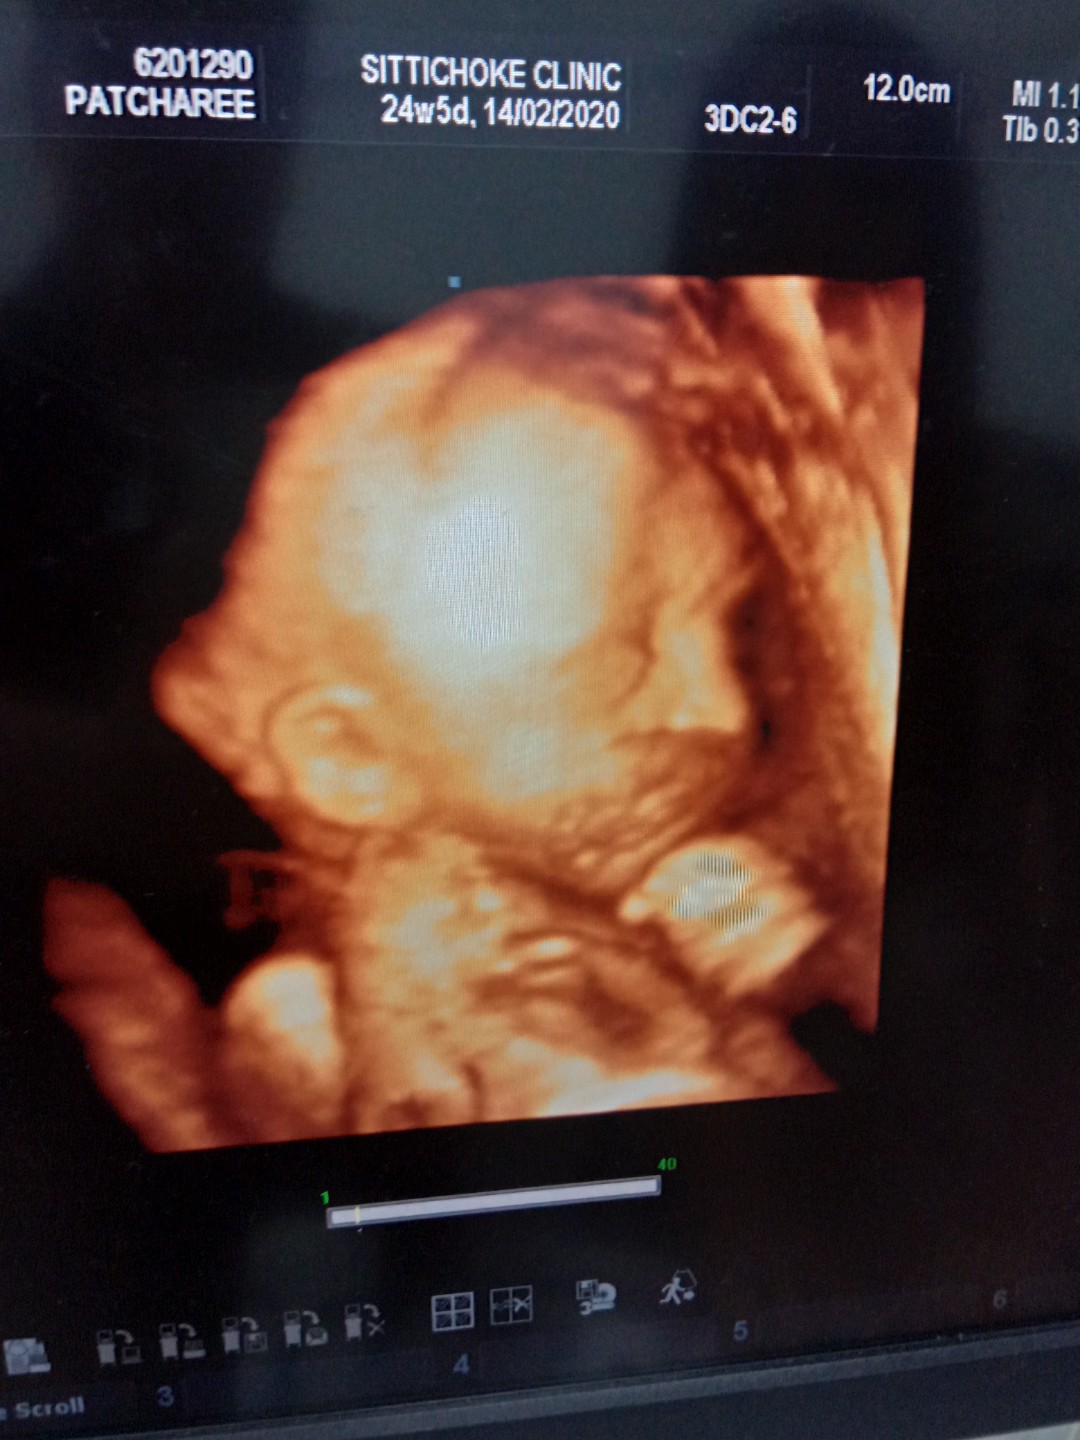

ของเรา1000บาทค่ะ ตอนอายุครรภ์24วีคค่ะ